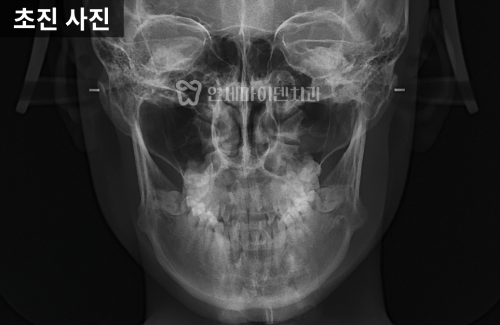

방사선 사진을 분석해 보니

위턱보다 아래턱이 발달한 3급 부정교합,

흔히 '주걱턱'이라고 하는 상태였습니다.

정면 방사선에서는

위턱과 아래턱의 폭 차이가 정상보다 훨씬 커서

위턱이 약 10mm 이상 좁은 상태가 확인됐습니다.